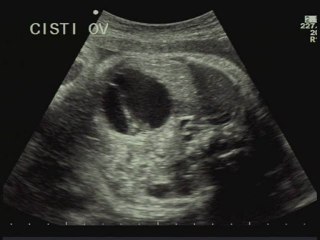

Aneurisma del forame ovale